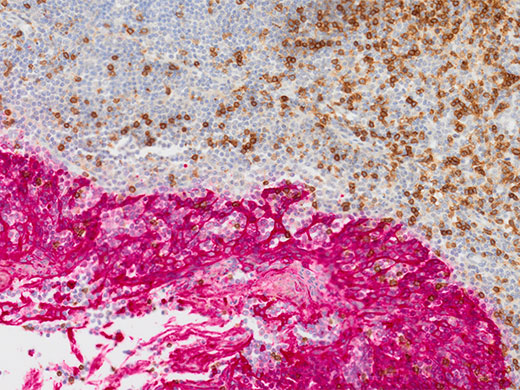

癌症和干细胞研究扁桃体CD3(rm),ImmPRESS试剂(HRP)抗小鼠IgG Immpact DAB(棕色),AE1/AE3(m)ImmPRESS(AP)(HRP)抗兔IgG Immpact Vector Red(红色)。 用苏木精QS(蓝色)复染。 图像数据承蒙Vector实验室提供。 |